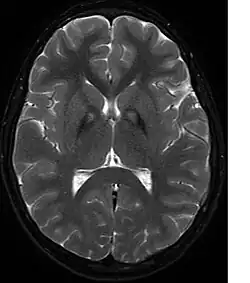

T2-gewichtetes MRT

Neben dem laborchemischen Ausschluss eines Morbus Wilson, fakultativ auch einer Neuroakanthozytose, führt vor allem eine kernspintomographische Untersuchung des Gehirns zur Erhärtung der Diagnose. Hier zeigt sich in T2-gewichteten Aufnahmen im Globus pallidus charakteristischerweise eine durch Eisenablagerungen bedingte Hypointensität mit einer zentralen, vermutlich durch eine Gliose bedingten Hyperintensität. Dieser charakteristische Befund wird als „Tigerauge-Zeichen“ (englisch eye of the tiger) bezeichnet und findet sich bei allen Patienten mit PANK2-Mutationen. In einer genetischen Untersuchung lassen sich ggf. Mutationen im PANK2-Gen nachweisen. Eine sichere Diagnosestellung kann nur neuropathologisch erfolgen.